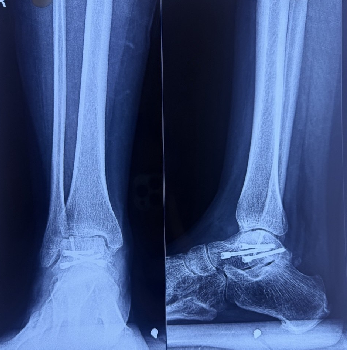

Lisfranc Injury Treatment

Lisfranc injury treatment includes immobilization, rest, pain management, and physiotherapy. Moderate to severe cases may require surgical fixation, followed by structured rehabilitation programs to restore stability, improve mobility, and ensure proper long term recovery.